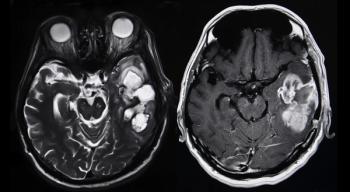

The addition of bevacizumab to lomustine for patients with progressive glioblastoma did not result in a significant improvement in overall survival.

More than 25% of patients with recurrent, high-grade glioma treated with a gene therapy combination were alive more than 3 years after treatment, according to data from a subset of patients in a phase I clinical trial.